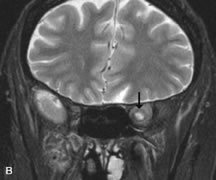

MRI is also effective in imaging orbital tumors of mesenchymal origin, such as rhabdomyosarcoma, particularly in the assessment of extension into the anterior and middle cranial fossae (Fig. 17).37 The lack of any pathognomonic radiologic features necessitates rapid orbital biopsy when rhabdomyosarcoma is suspected.

Fig. 17. A. T1- and (B) T2-weighted MR scans demonstrate a preseptal and extraconal mass displacing the globe medially. The mass is slightly hyperintense on the T1-weighted scan and very hyperintense on the T2-weighted scan owing to the high extracellular water content of the neoplasm. The lesion abuts the globe and appears to infiltrate the lateral rectus muscle (arrow). C and D. Postcontrast fat-suppressed T1-weighted scans demonstrate intense enhancement of the highly infiltrative lesion that is invading the lateral rectus, superior rectus, and levator palpebrac superioris muscle (double arrows).